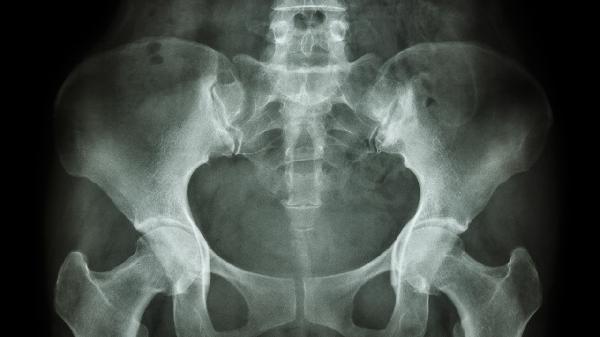

右侧筛窦骨瘤是一种良性骨性肿瘤,主要发生在筛窦等颅面部的骨结构中,多表现为缓慢生长且症状隐匿,但若肿瘤增大可能压迫周围组织,引起面部痛感、头痛、鼻塞或视力受损等症状。尽管这种病通常是无害的,但某些情况下仍需要治疗。

筛窦骨瘤的形成原因尚未完全明确,通常与遗传因素以及慢性炎症刺激有关。例如,家族中骨瘤病史可能增加患病风险,而长期反复的鼻腔或鼻窦炎症,也可能刺激骨组织异常增生。骨结构发育异常与外伤也可能在某些情况下诱发骨瘤。筛窦骨瘤大部分以无症状的形式被发现,多见于影像检查中偶然被确诊。如果肿瘤压迫邻近的鼻腔或眼眶组织,患者可能会出现持续性鼻塞、反复的鼻窦感染、眼部突出的表现,甚至出现视力下降。